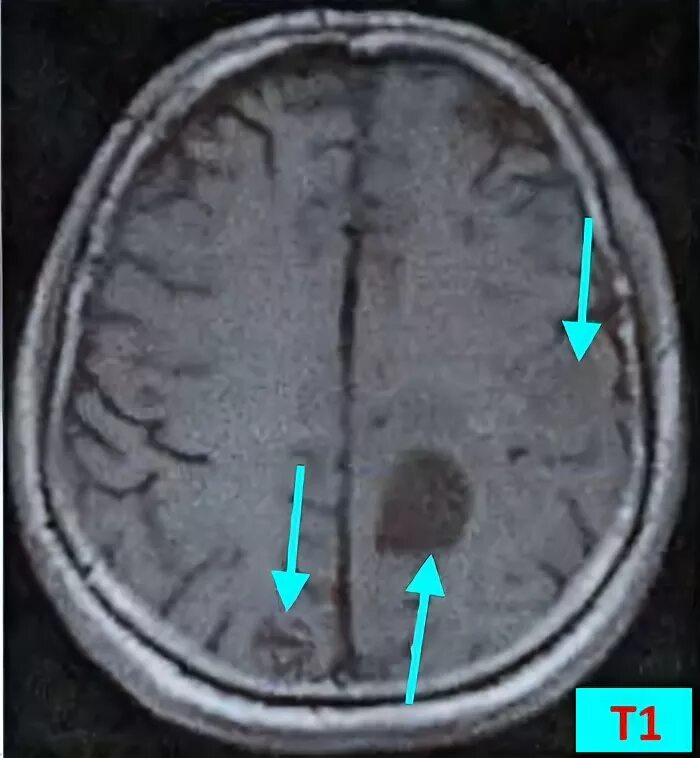

Отек мозга метастазы